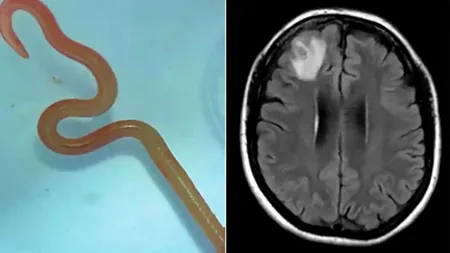

Un vierme, care sălășuiește de obicei în pitoni, s-a aciuit în creierul unei femei din Australia. De unde poate proveni parazitul buclucaș